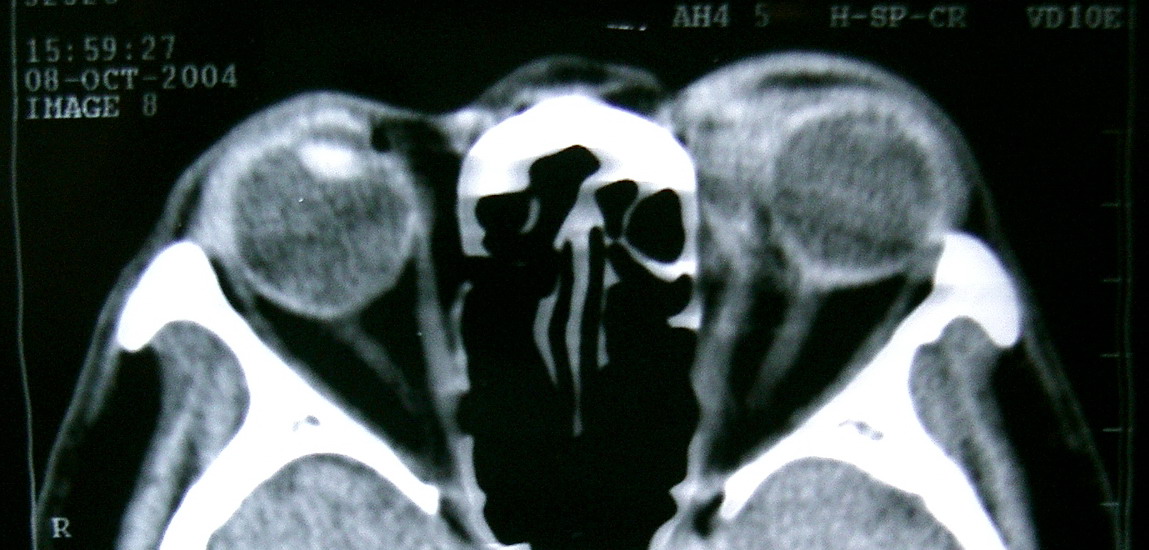

眼眶冠扫,平扫CT:

左眼球内上方可见不规则软组织块影,大小约2.5*1.0CM,与邻近组织分界不清,相邻之内直肌、上直肌增粗,眼环正常,眶壁骨质无破坏,左上颌窦底部可见粘膜增厚,其余副鼻窦未见异常。

IMP:1,左眼眶肿物;2,左上颌窦炎